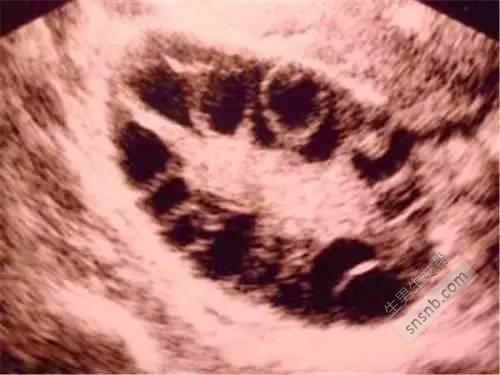

医生告诉我,我是多囊卵巢综合征。让我老公也来检查,他一开始不愿意来,后来在我再三恳求下检查了。结果没有一点问题,他嘲笑我,说我想把责任推给他,明明是我妈没给他一个好身体的闺女。我也一直觉得,是自己有问题,不能怪他骂我。

然后,我开始了三年的吃中药,吃西药,促排。循环,我们这边的医院,只要是生殖科的医生没有一个人不认识我的。因为我跑医院的次数,几乎是只有他们休息我才会不去。(所有的费用全是我自己负担,或者妈妈给我)医生要求我重新检查输卵管。因为我已经促排了8次了。